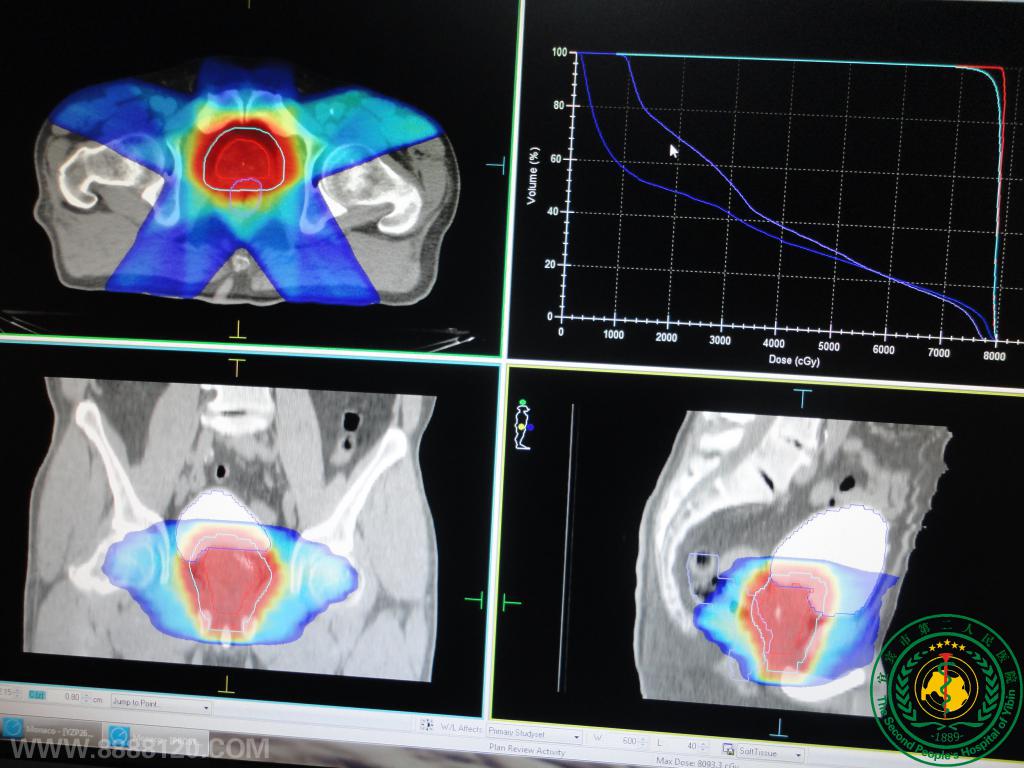

盆腔宫颈癌及头颈下咽癌、喉癌VMAT调强靶区高剂量、正常组织低剂量及剂量验证高度吻合